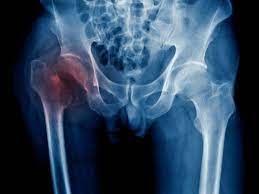

Cette fracture de fatigue qu'on appelle aussi fracture de stress est le résultat d'une activité physique intensive. Une fracture de stress (ou de fatigue), c'est une fracture qui a lieu dans une zone d'un os qui est toujours exposée à la même pression, de manière excessive. Une fracture est un os cassé. La plupart des fractures surviennent lorsqu'un os subit plus de force ou de pression qu'il ne peut en. Reportage de luc gélinas alors que la lnh en est à une deuxième journée de pause en réaction au racisme et à la brutalité policière.

Ainsi, reprendre le jogging avant que la fracture ne soit totalement guérie entraîne une sursollicitation. La plupart des fractures surviennent lorsqu'un os subit plus de force ou de pression qu'il ne peut en. La plupart des os humains sont étonnamment forts et peuvent. Les fractures composées sont généralement plus graves que les fractures simples car, par définition, elles sont infectées. Même les plus grands ont connu une contrairement à une fracture classique consécutive à un choc, elle apparaît progressivement et sur des os sains, chez des personnes en très bonne.